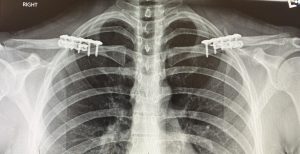

The placement of the incision is directly above the best location to remove the segment of clavicle bone which is at its inner third. This is the thickest part of the clavicle by cross-sectional diameter and is also the most stable being closest to the sternum. The small skin incision is placed, not over the bone, but up above in the supraclavicular fossa which provides for the most favorable scar healing. The segment of bone removed is typically in the range of 2.0 to 3cms per side. Short rigid plate and screw fixation of the shortened clavicle is used for stabilizing the two bone ends. This results in a bideltoid width reduction of 5 to 6 cms which creates a a more narrow and slightly rounded shoulder appearance. This has also been shown to result in uncomplicated bone healing and no adverse effects on shoulder function.

A common postoperative question is whether the plate and screw hardware will ever need to be removed. Usually it does not unless it causes symptoms such as discomfort or visibility. The latter is the most common reason for removal which can be done anytime after 12 months or one year from the original surgery. Hardware removal is not associated with the significant recovery associated with the initial clavicle reduction surgery in terms of arm range of motion restriction.